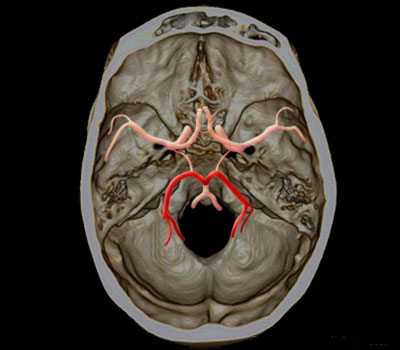

Artères cérébrales postérieure